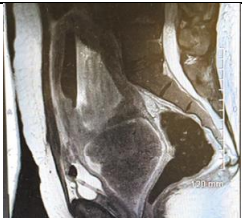

Ultrasound imaging revealed an enlarged and heterogeneous uterus with a non-vascular hypoechoic area and a hyper-echoic wall, suggestive of a necrotic fibroid or intrauterine fluid accumulation (Figure 1). These findings indicated advanced pathology within the uterine cavity.

Figure 1 Pelvic Trans abdominal ultrasound scan